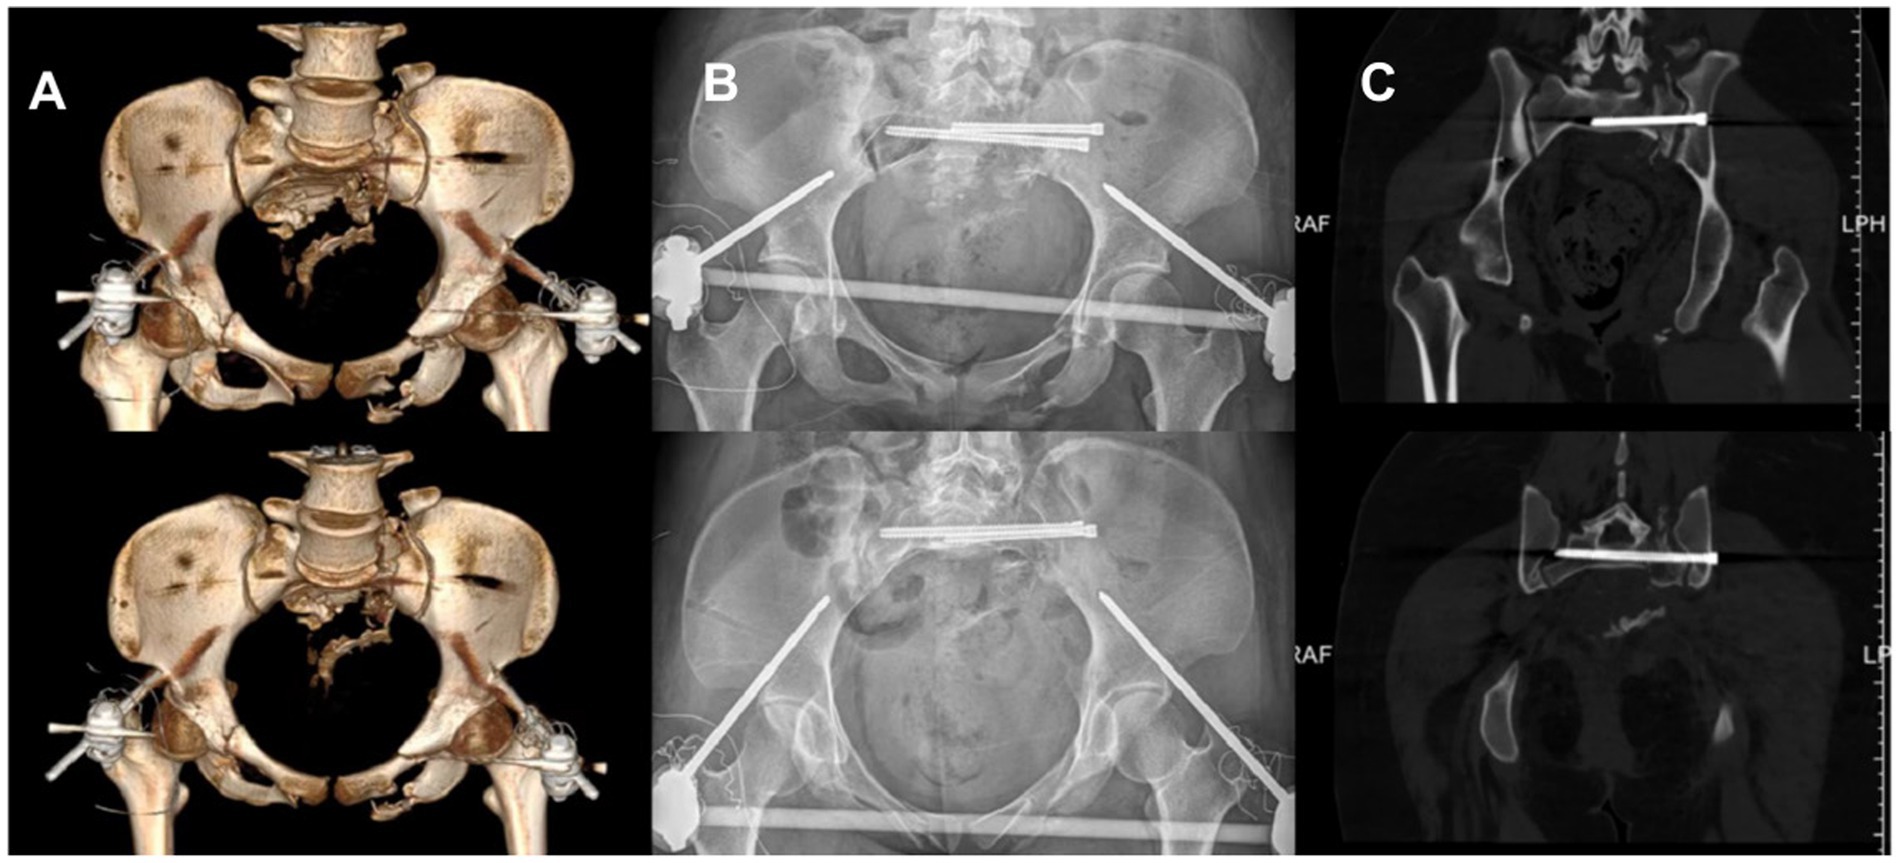

4.3 Follow-up results

The fixation was performed using a standard S1 sacroiliac screw combined with an extended S2 sacroiliac screw. The anterior ring was stabilized with an anterior inferior iliac spine external fixator. Immediate postoperative X-ray showed restoration of the pelvic axis and accurate screw placement. One week postoperatively, CT confirmed fracture reduction meeting the excellent criteria of the Matta standard Figure 5. At the 3-month follow-up, the patient reported no pain, normal hip joint range of motion, partial recovery of lower limb sensation and muscle strength, and imaging demonstrated good fracture healing with no signs of internal fixation loosening or fracture. The patient reported, “I can sit normally now, and walk with double crutches without help. I can also do some light daily activities like making the bed. The numbness in my lower back and thighs has gotten much better, and I’m confident about getting back to my daily life soon.”

Figure 5

Postoperative X-ray and 3D CT images demonstrated the patient’s postoperative outcome. (A) Postoperative CT three dimensional reconstruction. (B) Postoperative pelvic X-ray orthopantomogram and entrance position. (C) Postoperative CT plain scan of the pelvis.